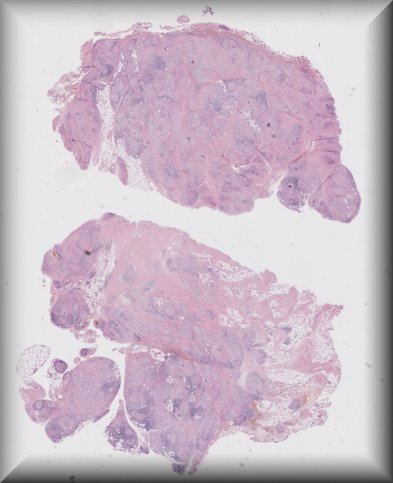

María Miguelina de la Garza Bravo (Houston): 53-year-old male with a 10-year-old history of bilateral exophthalmos (R>L), status post debulking. |

![]() |